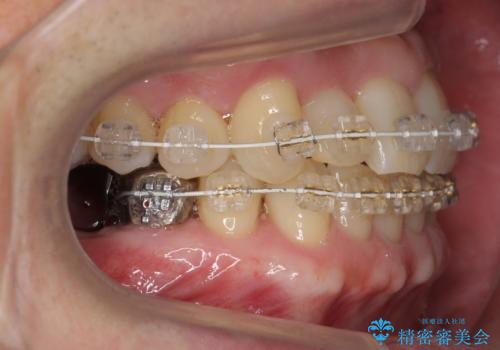

矯正治療後、右下のインレーブリッジおよび左下の銀歯のやりかえを行なっています。

右上の八重歯は、右上の奥歯を矯正用ミニスクリューを用いて遠心移動を行い解消しました。

下の前歯はIPR(エナメル質を薄く削り歯を小さくする処置)を行なっています。